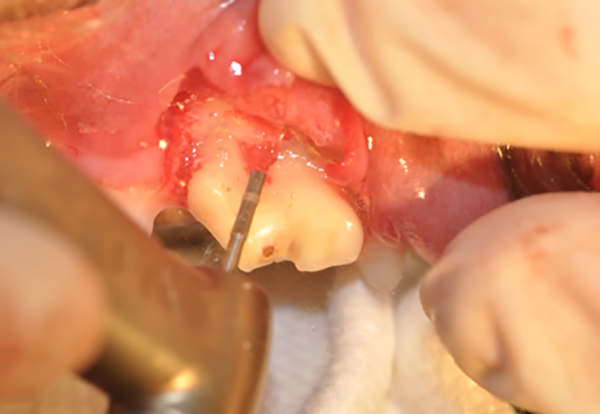

Figure 2B : Après l’élévation du lambeau, l’os alvéolaire est fraisé sur un tiers de sa hauteur (alvéolotomie) à l’aide d’une fraise boule montée sur une turbine ou un contre-angle multiplicateur, une irrigation abondante est nécessaire.